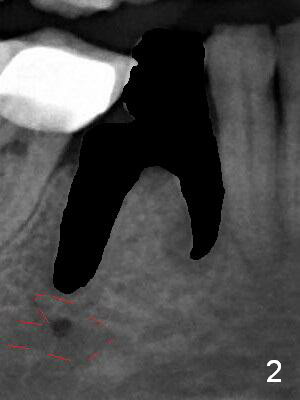

The patient returns for implant placement 11 months post extraction of #28 and 29. With flapless manner, initial osteotomy happens to drop into the original socket of #28 (Fig.4). After use of 3.3 mm Magic Drill (MD) and Final Drill for 15 mm, a 4x11 mm dummy implant is placed (Fig.5). It appears that the implant is long for the site (red dashed line: Mental Loop). However, a definitive implant (4x9 mm, IBS) has difficulty to reach its depth (Fig.6). After several rounds of untorque and retorque, the implant does not seat completely (Fig.7, implant driver disengagement) with autogenous bone placed distal (>). Retrospectively, a larger MD should have been used (3.8 mm) for complete seating in the dense bone. In fact she is post breast cancer treatment with 50% chance of relapse. The patient returns for follow up 1.5 months postop (Fig.8). The wound has healed. Impression is taken 5 months postop (Fig.9). When the crown is cemented, food impaction is an issue between the implant crown and crown at #30. Since the tooth #30 is mesially tilted with distal open margin and apical infection, the tooth will be extracted. Osteotomy is going to be initiated in the mesial slope of the mesial socket (Fig.9 red line). An implant will be placed more or less in the mesial socket (green box).